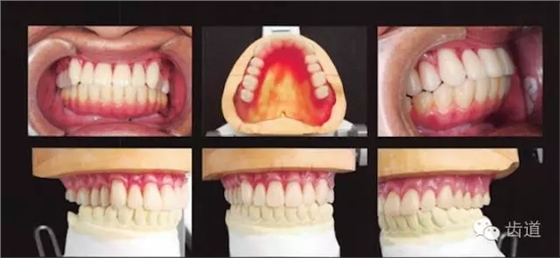

看阿部老師怎么做? 1、與患者充分溝通治療的難點(diǎn)和可能出現(xiàn)的問(wèn)題 2、上頜用松軟牙齦的印模技術(shù),由后方按壓,使松軟的部分立起,取無(wú)壓力開(kāi)窗式印模 3、加厚前牙區(qū)的邊緣厚度,使之在前鼻嵴處獲得支撐 4、做好后緣封閉 5、人工牙怎么排列才能穩(wěn)定? 前牙按正常覆he覆蓋進(jìn)行排列 雙尖牙內(nèi)收,排列在牙弓的穩(wěn)定區(qū)間 咬合平面只能按無(wú)法修正的下頜種植義齒進(jìn)行排列 6、繼續(xù)在口內(nèi)試咬,逐一調(diào)整每個(gè)牙的位置,以防止義齒的翹動(dòng)和不穩(wěn)定 7、最終的義齒采用舌側(cè)集中he型 阻止翻復(fù)的排牙方式 選擇高精度的義齒聚合方法 前牙唇側(cè)基托保持有支撐作用的厚度 容易形成支點(diǎn)的區(qū)域以組織調(diào)整劑(TC)進(jìn)行調(diào)整 完全適應(yīng)后,將襯墊的極小區(qū)域置換成常溫聚合樹(shù)脂 8、義齒配戴完成 多虧患者的咀嚼方式良好,義齒戴入后既不疼痛,也不會(huì)脫落!